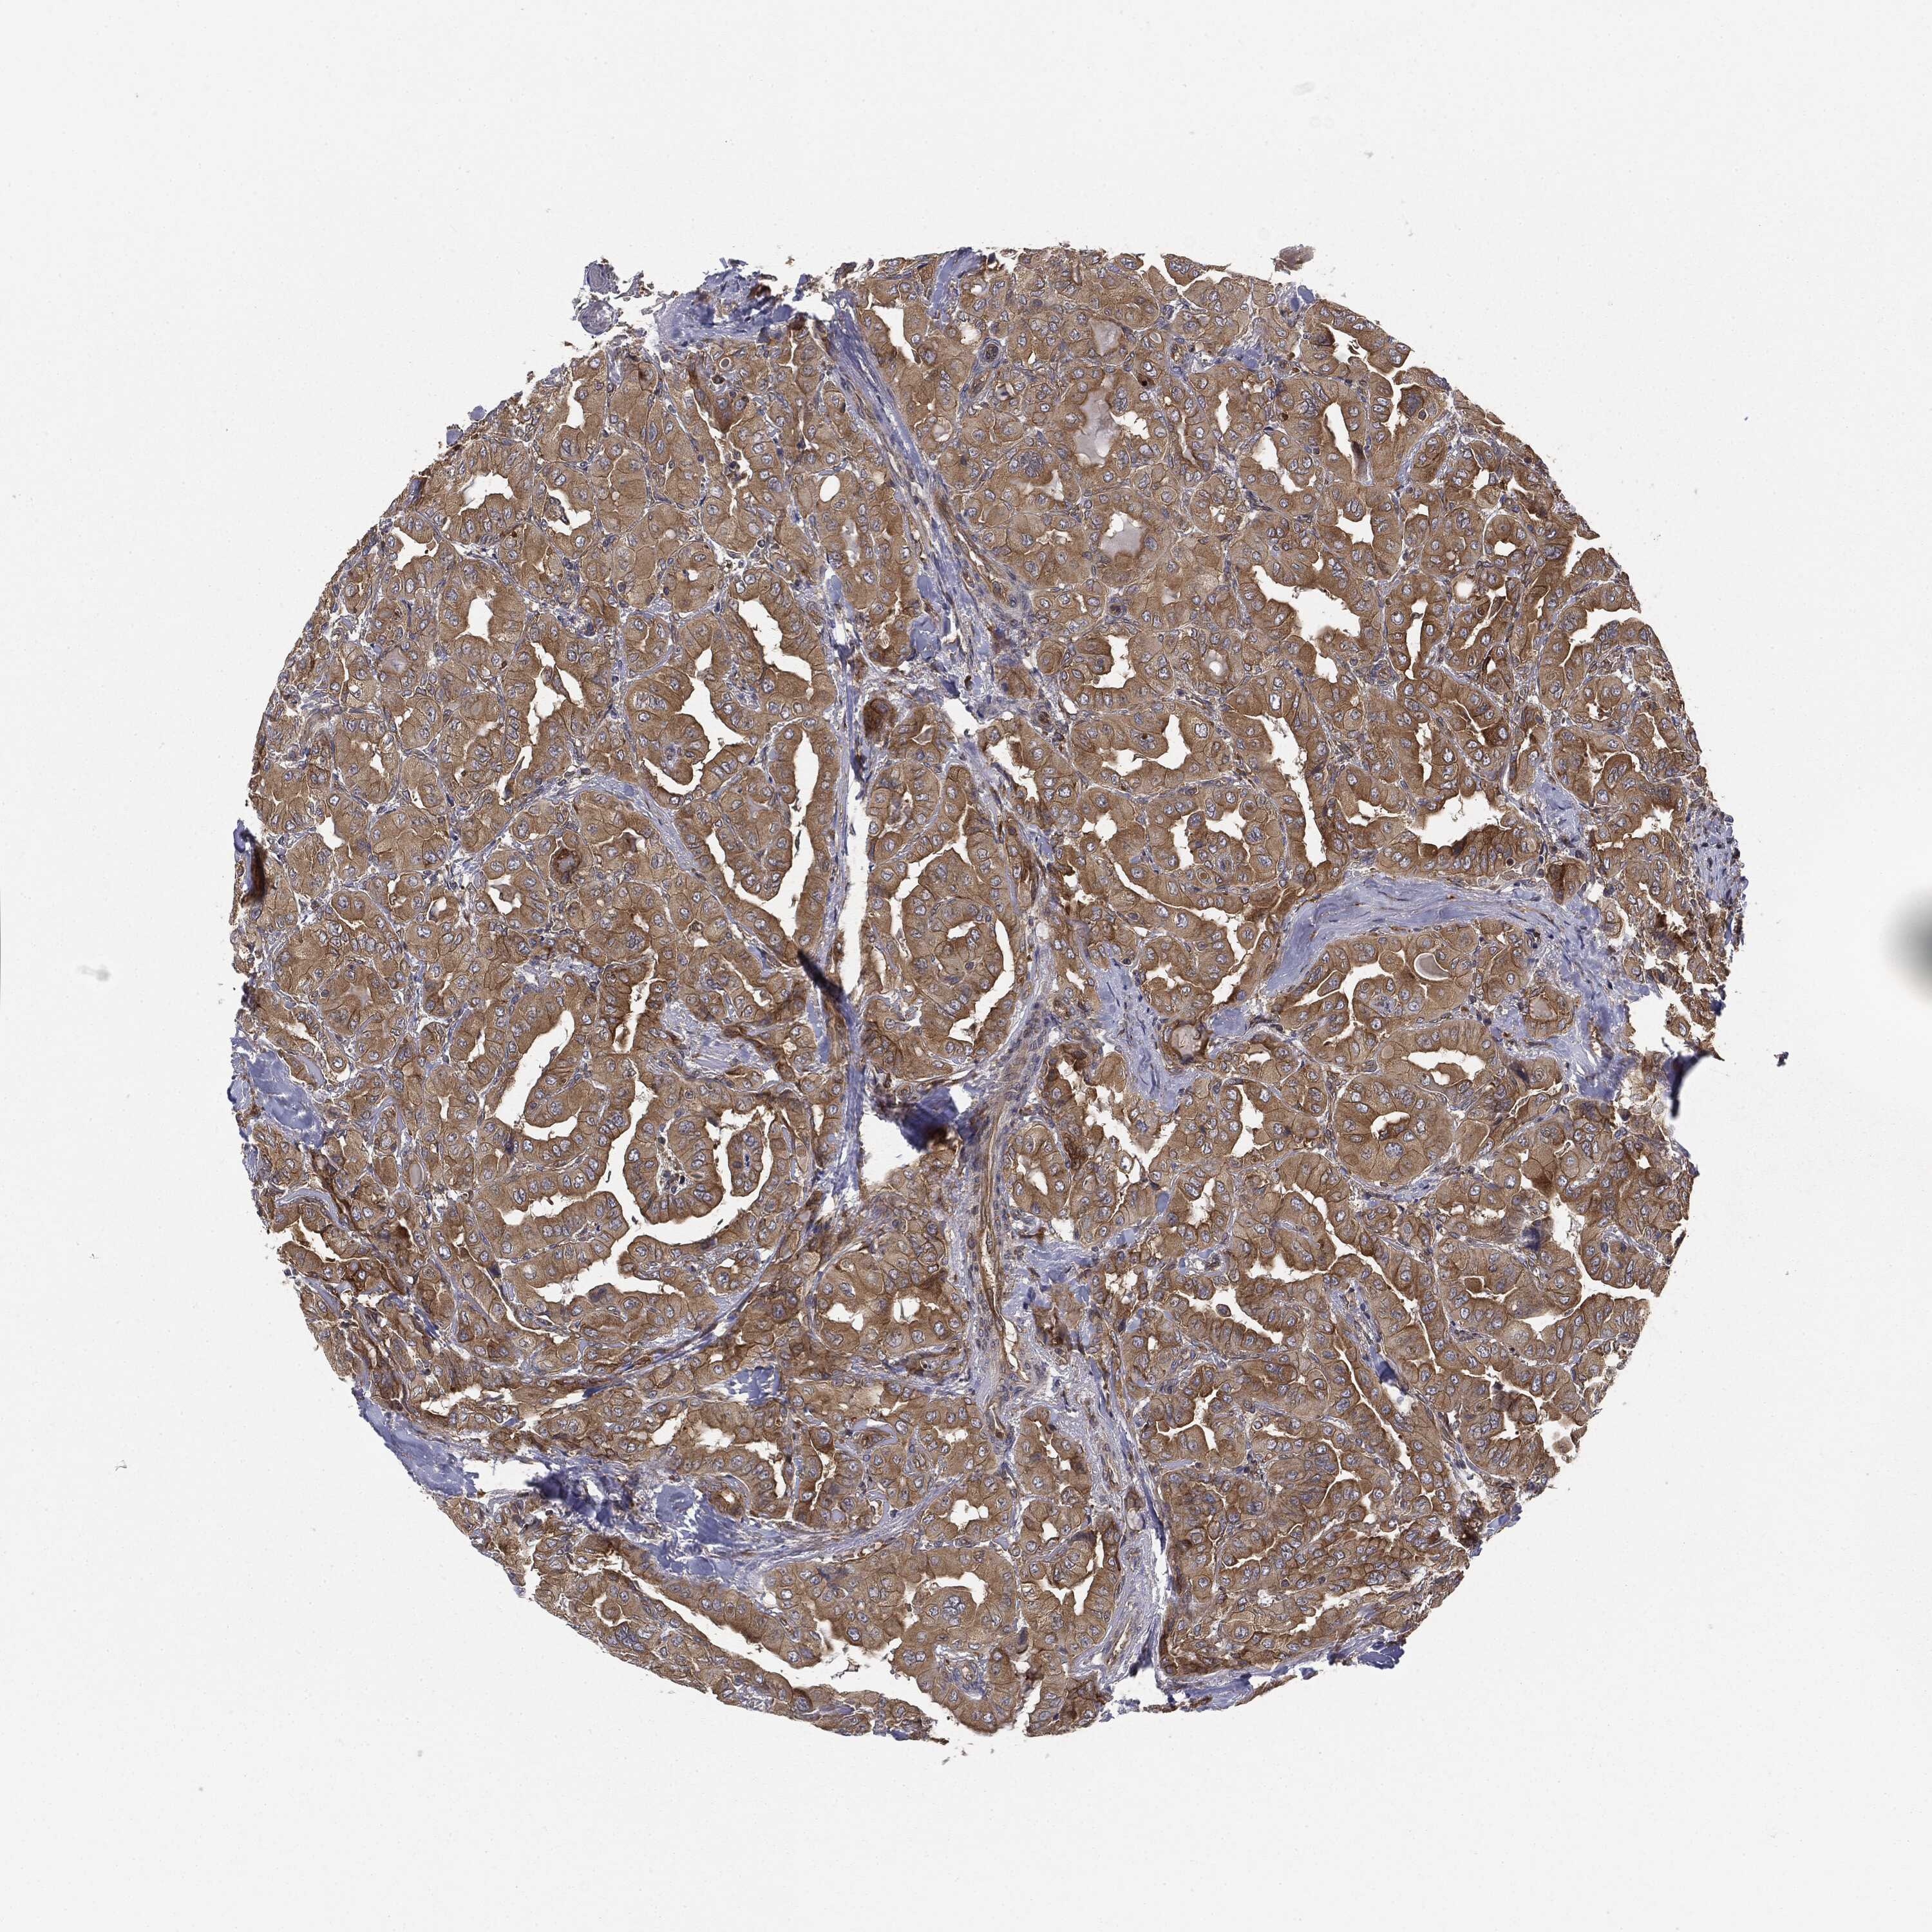

THYROID CANCER - Protein expressioni

A mouse-over function shows sample information and annotation data. Click on an image to view it in a full screen mode. Samples can be filtered based on level of antibody staining by selecting one or several of the following categories: high, medium, low and not detected. The assay and annotation is described here.

Note that samples used for immunohistochemistry by the Human Protein Atlas do not correspond to samples in the TCGA dataset.

Antibody stainingi

Antibody staining in the annotated cell types in the current human tissue is reported as not detected, low, medium, or high, based on conventional immunohistochemistry profiling in selected tissues. This score is based on the combination of the staining intensity and fraction of stained cells.

Each image is clickable and will lead to virtual microscopy that enables deeper exploration of all samples and also displays staining intensity scores, fraction scores and subcellular localization as well as patient and tissue information for each sample.

Antibody HPA019795

Antibody HPA063893

Antibody CAB003845

Staining

High

Medium

Low

Not detected

Intensity

Strong

Moderate

Weak

Negative

Quantity

>75%

75%-25%

<25%

None

Location

Nuclear

Cytoplasmic/membranous

Cytoplasmic/membranous,nuclear

Papillary adenocarcinoma, NOS

Follicular adenoma carcinoma, NOS

Carcinoma, NOS